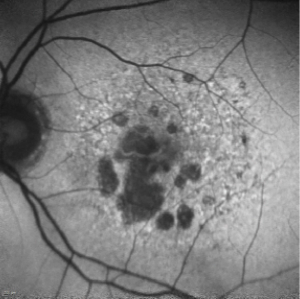

A deeper look at pegcetacoplan

The first approved GA treatment leaves room for additional therapies.